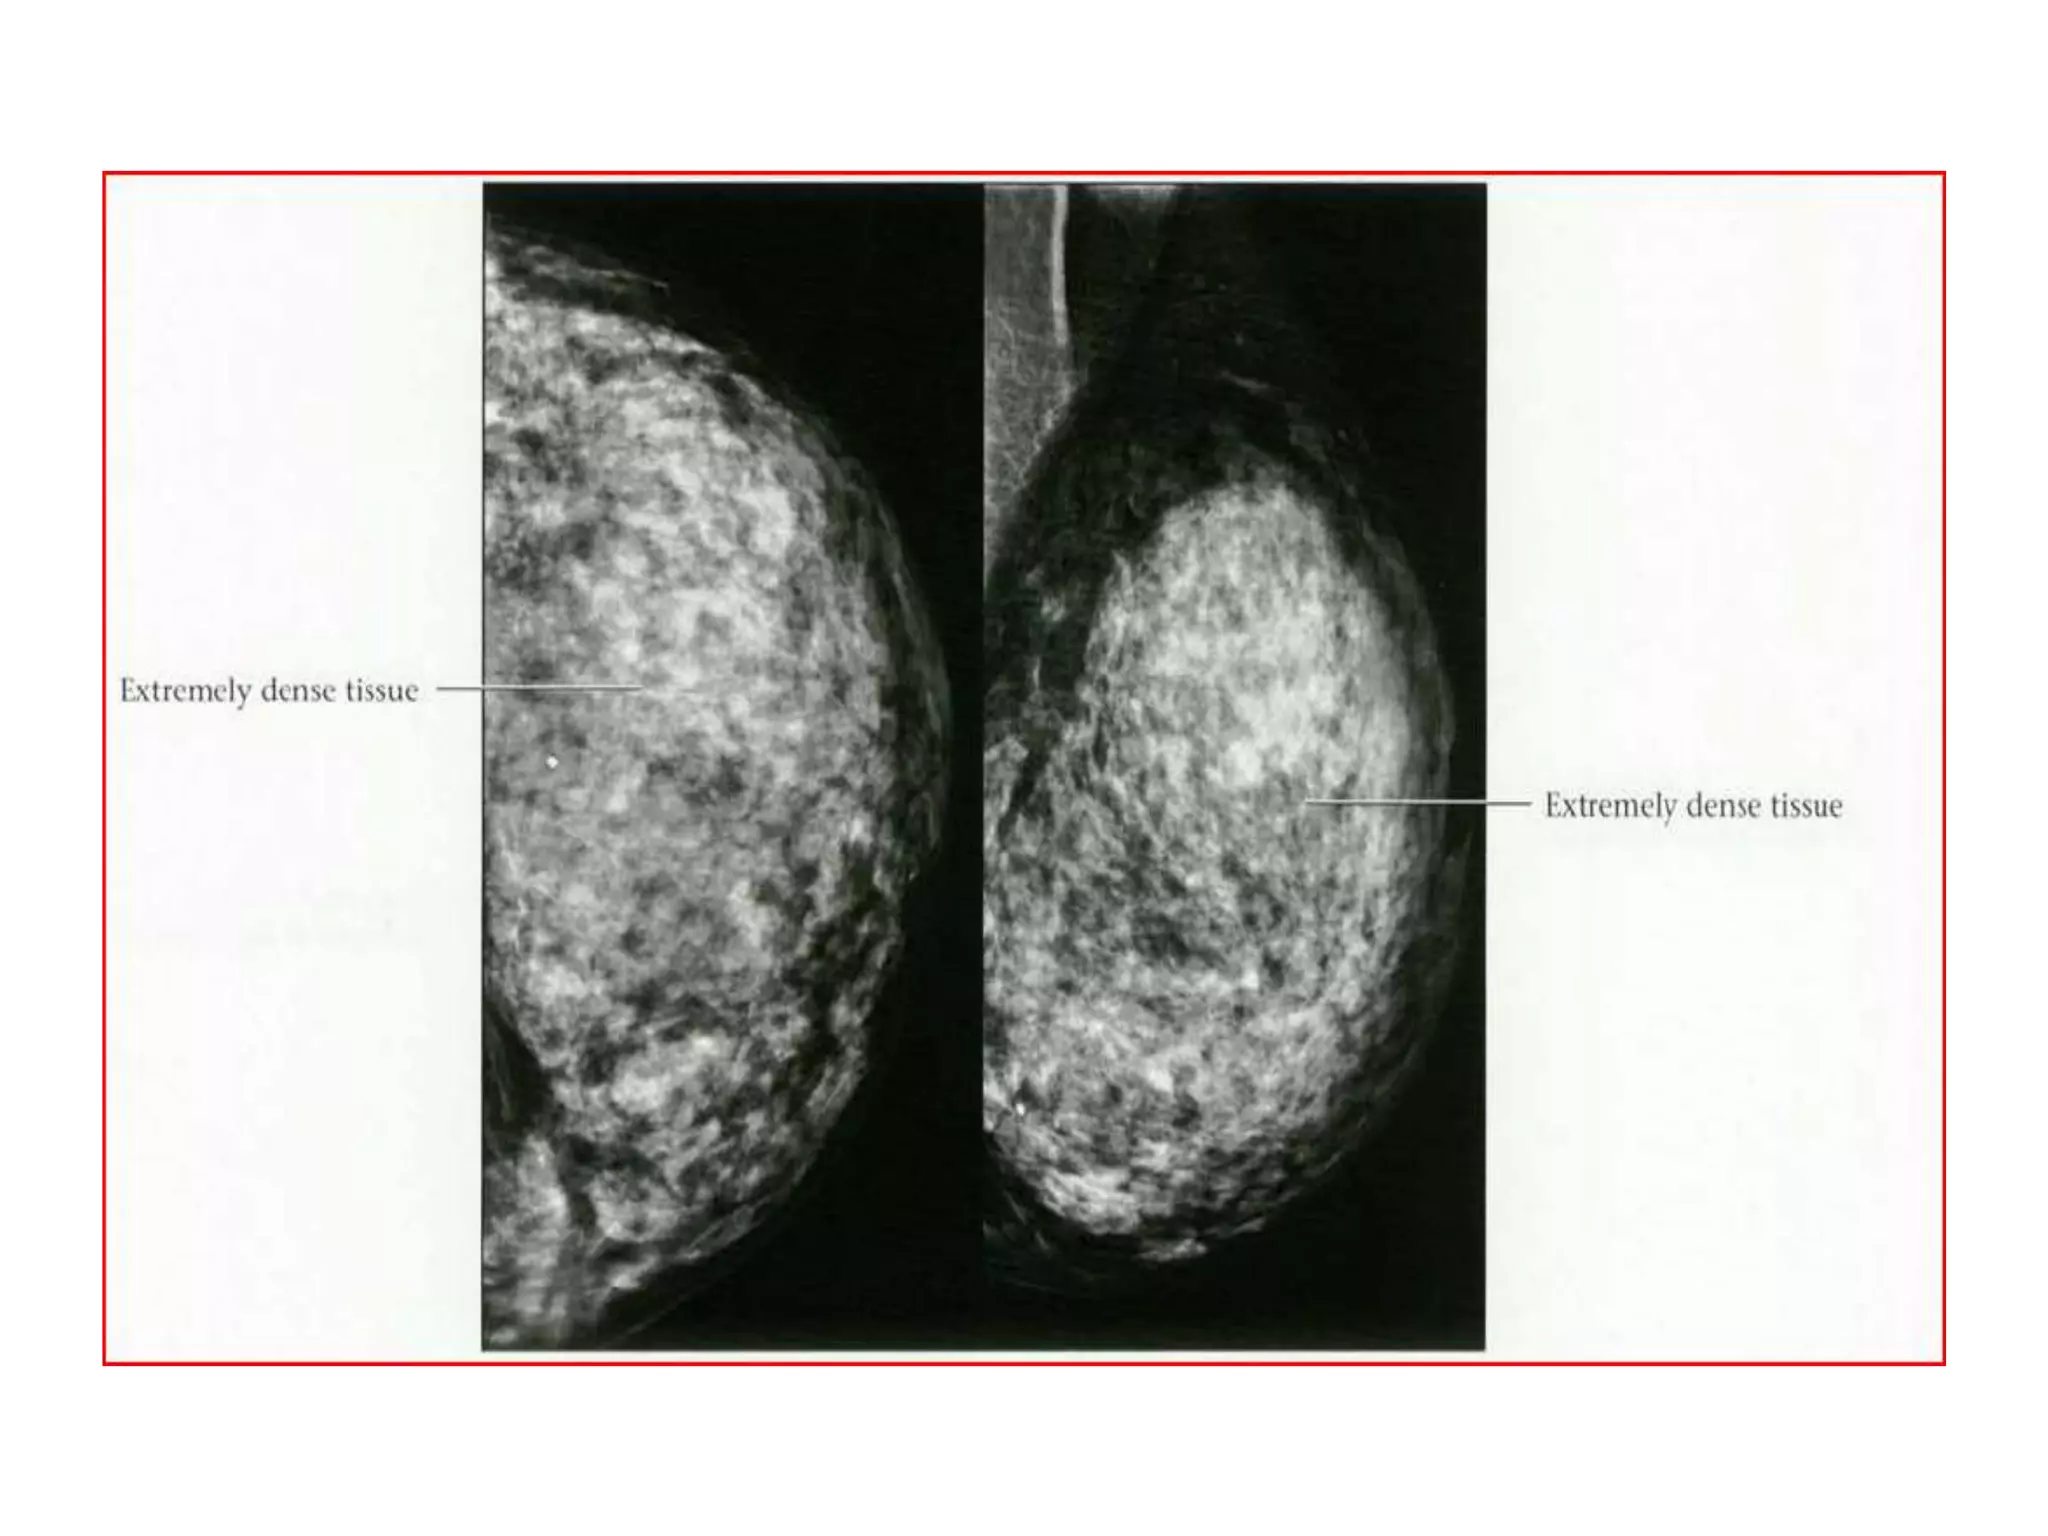

BI-RADS BREAST COMPOSITION

• The American College of Radiology Breast

Imaging and Reporting Database System (BIRADS)divides breast composition into four

categories:

• 1) almost entirely fat,

• 2) scattered fibroglandular densities

(approximately 25-50% glandular),

• 3) heterogeneously dense (51-75% glandular),

• 4) extremely dense (greater than 75% glandular).